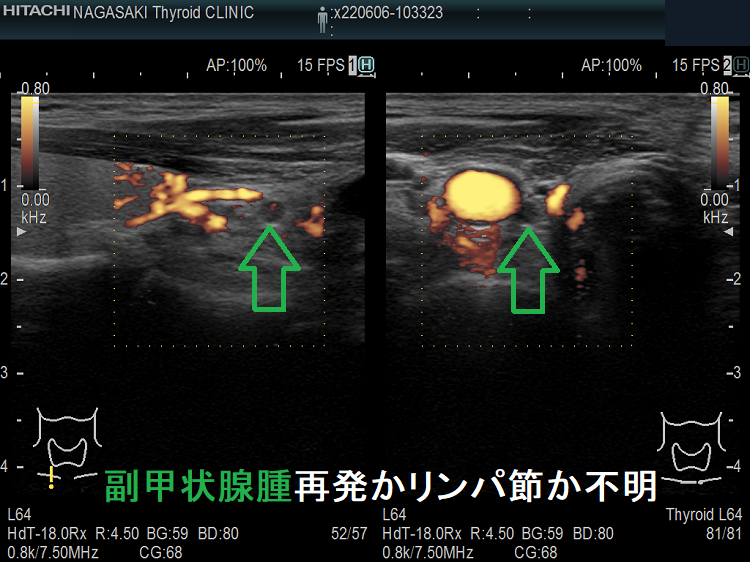

副甲状腺腺腫の取り残し、あるいは副甲状腺癌の再発か、リンパ節か分かりにくい場合があります。